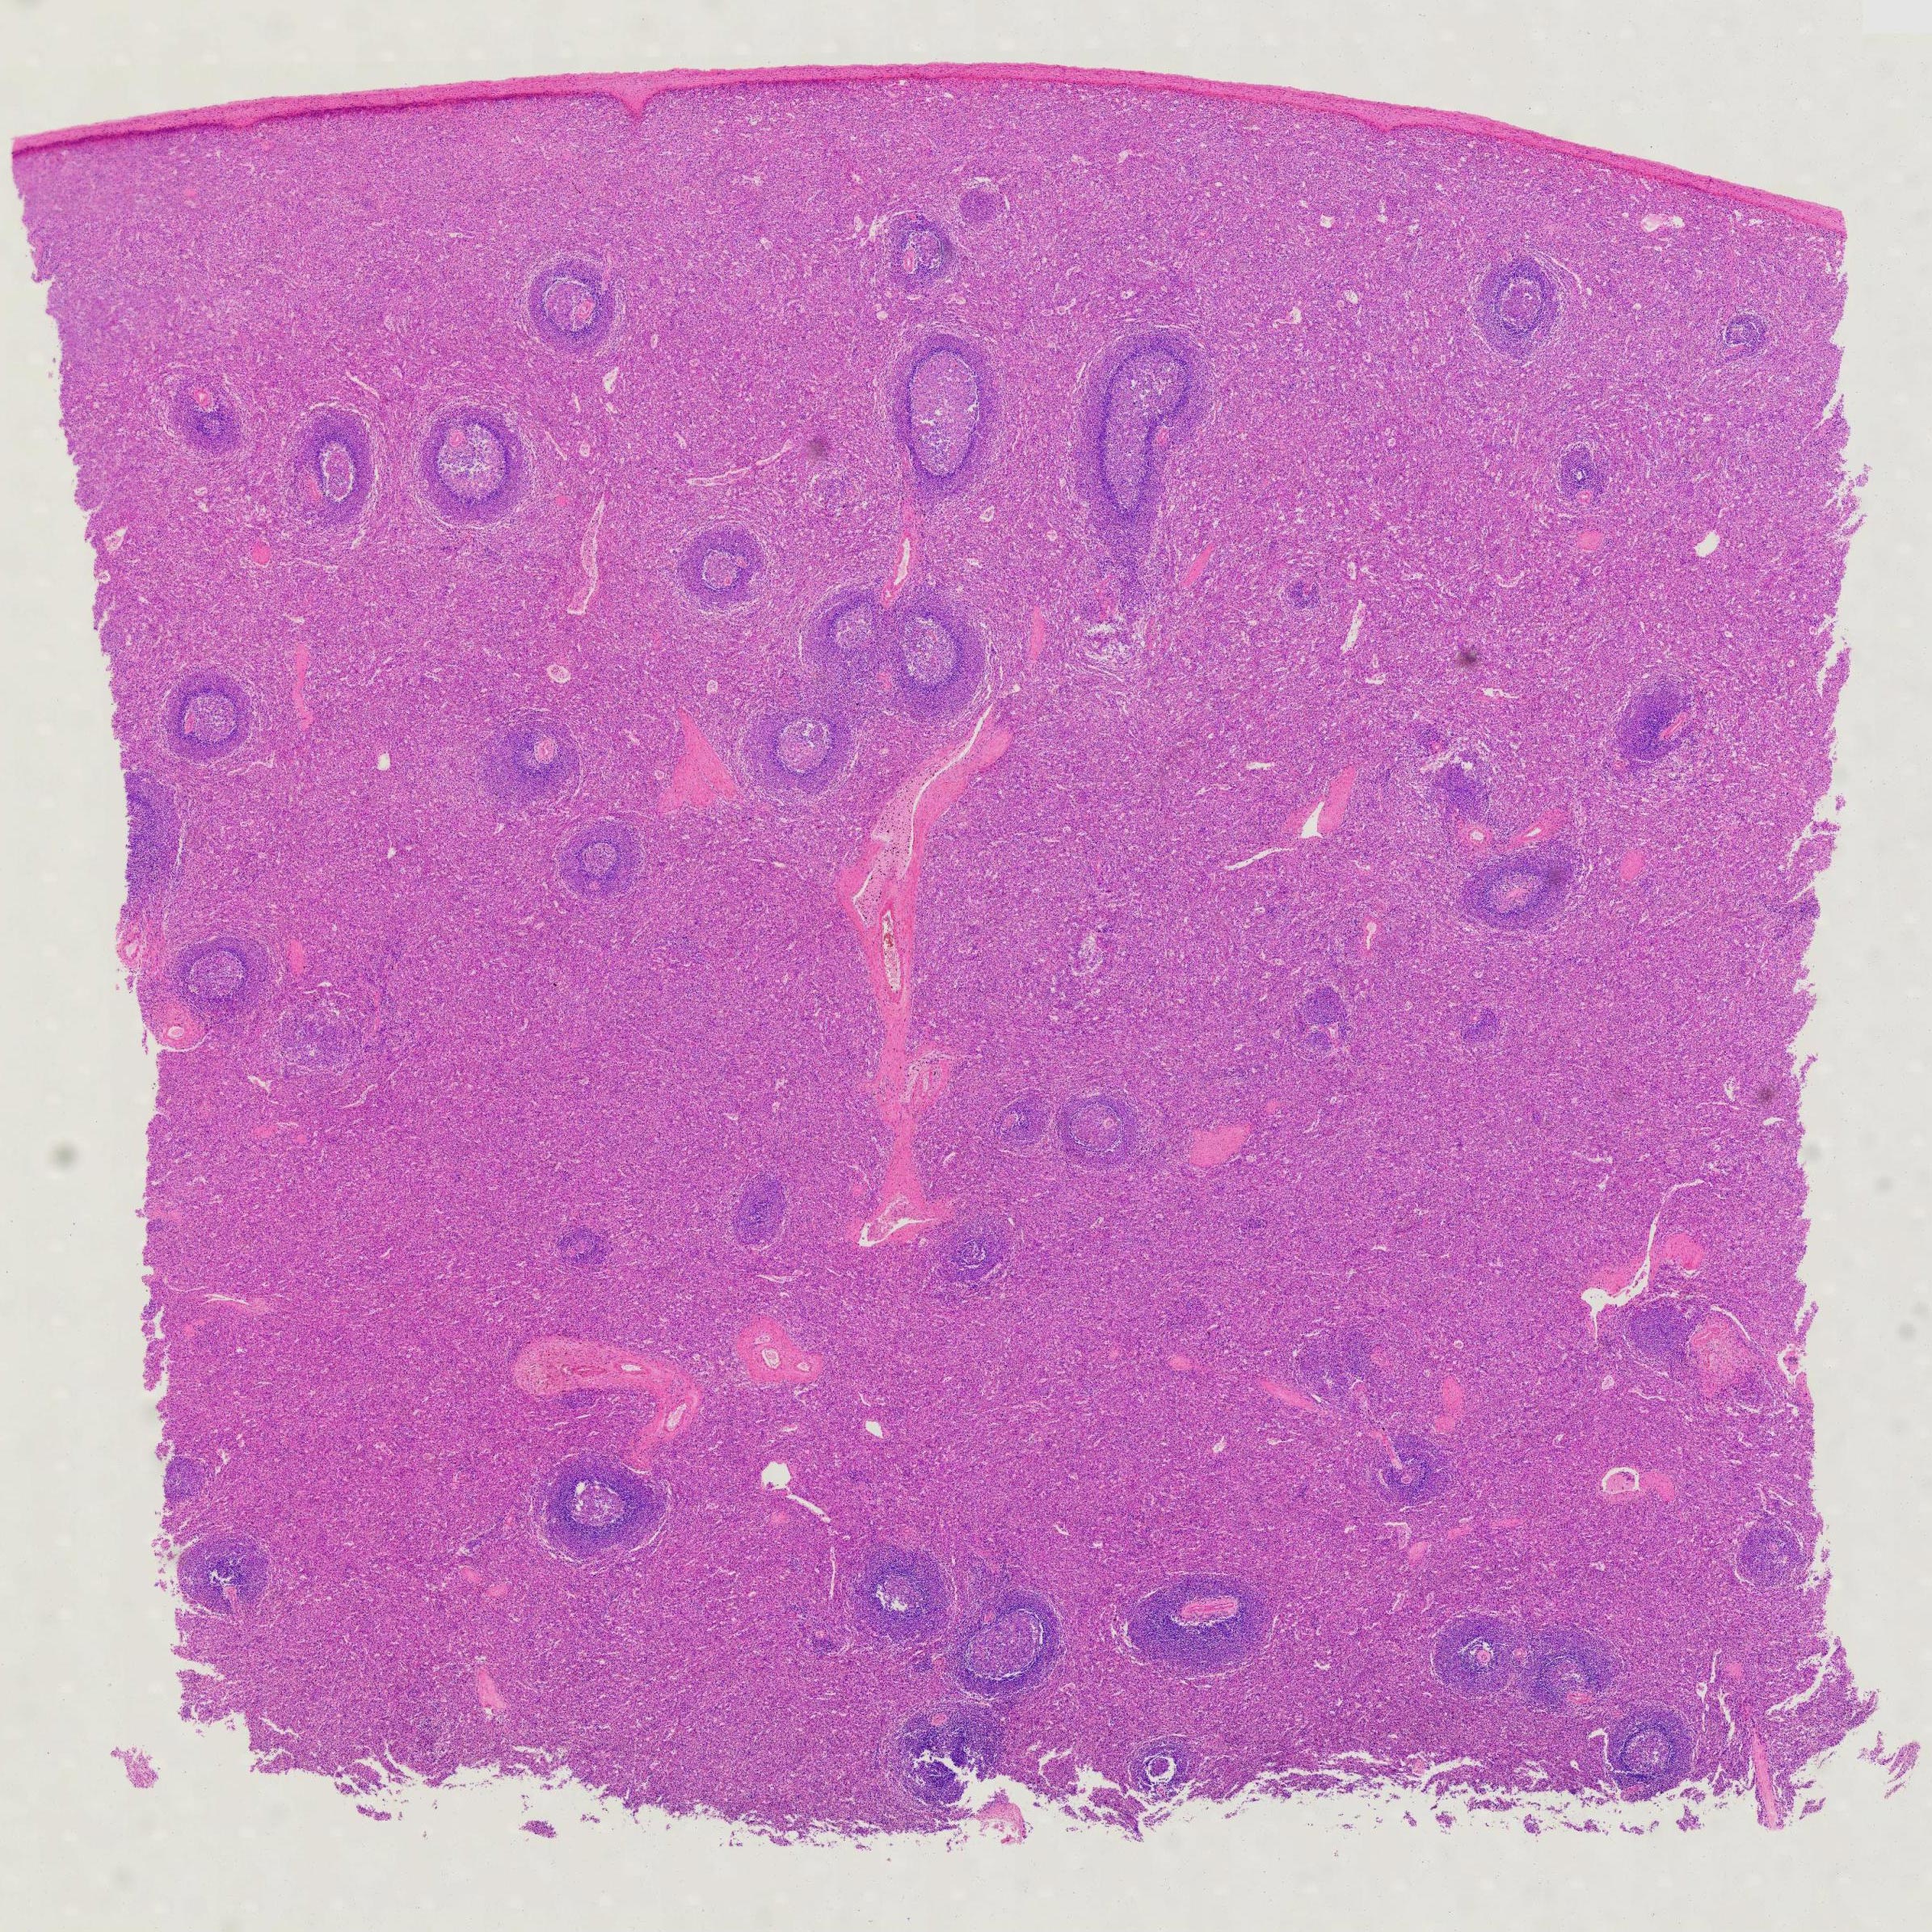

1pcs Human Spleen section, H.E. Stained, prepared microscope slides China wholesale supplier

Human Spleen Section

Thickness: 7-micrometer section

Stain: hematoxylin and eosin

1pcs Human spleen section, H.E. Stained, prepared microscope slides China wholesale supplier

Scientific name: Human spleen section

Description of the Human spleen section:

- Size: 76.2*25.4mm

- Thickness: 7-micrometer section

- Stain: hematoxylin and eosin

- Show: red pulp, splenic nodule, central artery